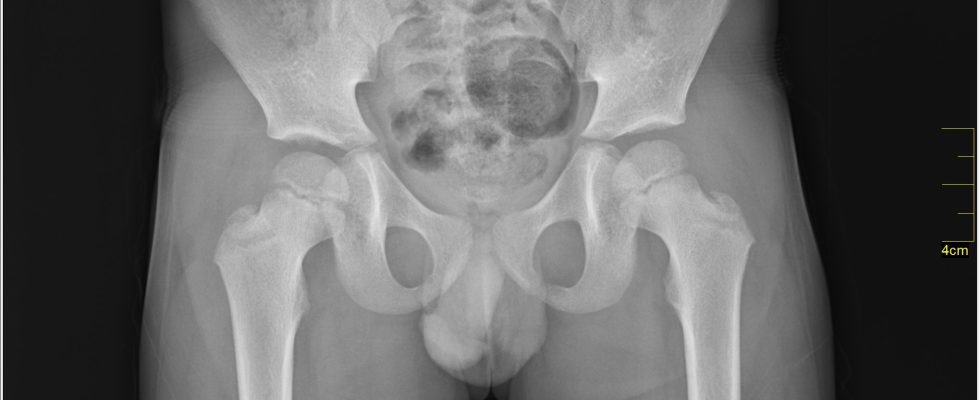

A car jumped the curb while exiting a parking lot, hitting a 61-year-old woman who was standing on a sidewalk in Queens, New York. The injuries that she sustained during the crash included a hip injury and pelvic fracture that required surgery to implant a metal pin to repair the broken bone. She was hospitalized for in-patient rehabilitation with physical and occupational therapy for 3 months. The pedestrian accident victim was left with chronic pain, decreased range-of-motion and will likely develop post-traumatic arthritis in those areas, according to her treating doctor. The woman filed a lawsuit against the driver for negligent operation of a vehicle, claiming that this negligence is what caused the accident and her permanent injuries. The driver of the car claimed that he had lost consciousness just prior to the car crash and should not be held responsible for the accident. However, the car accident victim secured the services of Morrison & Wagner LLP, who helped mediate a pre-trial settlement of $425,000 for her injuries as well as her residual pain and suffering. For more of our success cases please check out this link.

Illustrative photo by Nevit Dilmen © [CC BY-SA 3.0 or GFDL], via Wikimedia Commons